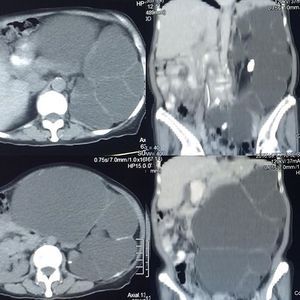

Hydronephrosis